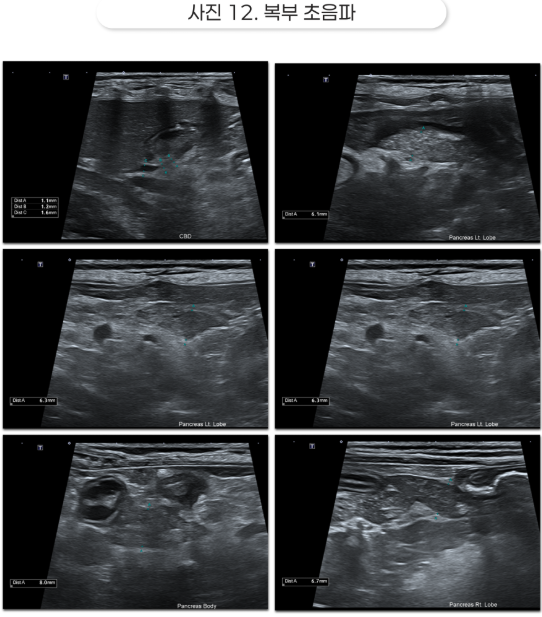

복부 초음파

초음파를 관찰했을 때 췌장 주변부에 소량의 복수가 확인되었습니다.

또한 지방이 다른 장기 주변의 지방보다 훨씬 하얗게 변해있었고, 췌장 자체의 밝기는 일반적인 췌장보다 더 크고 어둡게 관찰되었습니다.

이는 급성의 염증으로 인해 췌장에 부종이 발생할 경우 확인되는 소견으로, 주변 지방은 췌장의 염증 물질로 인해 자극을 받아 지방의 괴사 혹은 지방염으로 진행 중임을 짐작해 볼 수 있었습니다.

복수의 존재는 췌장의 염증이 오랜 기간 지속되어 발생했을 것으로 의심되었습니다.

또한, 빌리루빈 수치가 정상 이상으로 오르고 초음파상 췌장 실질이 염증으로 인한 괴사와 화농성 복수, 담즙의 배출이 원활하지 않아 발생하는 담관의 확장이 관찰되는 등 EHBO 발생 소견이 확인되었습니다.

초음파상 담관의 확장, 췌장의 실질 부종과 괴사 소견 역시 해소되었으며, 복부의 팽만감이 사라지고 복부 통증을 더 이상 호소하지 않았습니다.